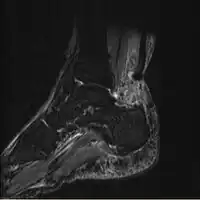

Imaging

Musculoskeletal ultrasonography can be used to determine the tendon thickness, character, and presence of a tear. It works by sending extremely high frequencies of sound through the body. Some of these sounds are reflected back off the spaces between interstitial fluid and soft tissue or bone. These reflected images can be analyzed and computed into an image. These images are captured in real time and can be very helpful in detecting movement of the tendon and visualising possible injuries or tears. This device makes it very easy to spot structural damages to soft tissues, and consistent method of detecting this type of injury. This imaging modality is inexpensive, involves no ionizing radiation and, in the hands of skilled ultrasonographers, may be very reliable.

MRI can be used to discern incomplete ruptures from degeneration of the Achilles tendon, and MRI can also distinguish between paratenonitis, tendinosis, and bursitis. This technique uses a strong uniform magnetic field to align millions of protons running through the body. These protons are then bombarded with radio waves that knock some of them out of alignment. When these protons return they emit their own unique radio waves that can be analysed by a computer in 3D to create sharp cross sectional image of the area of interest. MRI can provide unparalleled contrast in soft tissue for an extremely high quality photograph making it easy for technicians to spot tears and other injuries.

Achilles tendon rupture